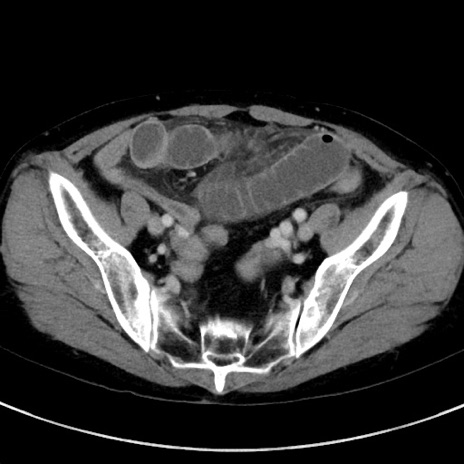

症例23(横断像)

【症例】70歳代女性

【主訴】下腹部痛・嘔吐

【現病歴】2日前より腹痛あり。昨日嘔吐あり。症状改善しないため来院。

【既往歴】胃GISTに対して胃部分切除後。

【身体所見】BT 37.1℃、BP 128/77mmHg、腹部:平坦・軟、下腹部に圧痛あり。

【データ】WBC 10200、CRP 0.31